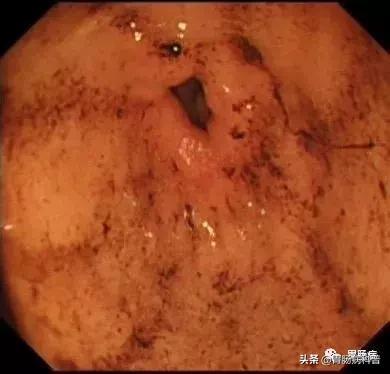

如下图:

在食道入口,距门齿约18至20cm处可见片状黏膜剥脱及条索状裂伤,持续渗血。

此时终于查明消化道出血原因,为患者的下一步治疗指明方向。